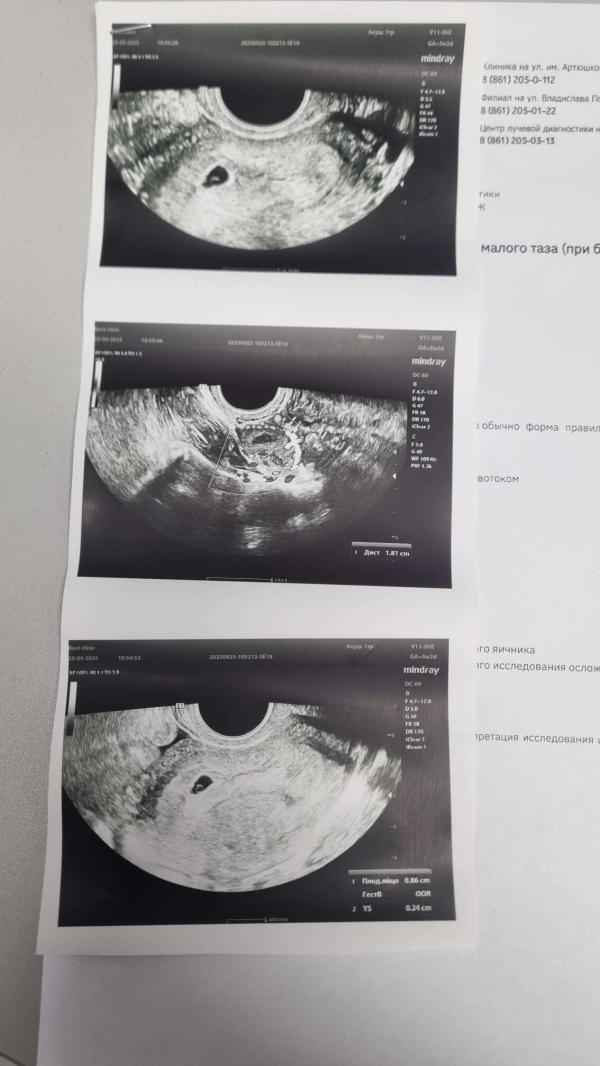

Иду на первое УЗИ (заведомо знаю ,что ещё сердечка не будет слышно), но уровень моей тревожности выше моих сил 🙈. Поэтому пошла убедиться ,что беременность маточная и всё в порядке.

Теперь как то надо вытерпеть 1,5 недельки перед ещё одним УЗИ ,что бы увидеть эмбриончик. Сейчас его не увидели...не знаю насколько это плохо или просто ещё слишком ранний срок ?!

На узи, по-моему ходила, в 6 недель, только желточный мешок был, потом (через 2 недели пошла), всё хорошо было, сердцебиение нашли. Оказывается, срок сильно разный был. На 2 недели разница с месячными. Вам лёгкой беременности ❤🌷

Если есть желточный мешочек , то и эмбрион скоро появится 💖 Легкой беременности вам и родов в срок 🌸😊

Мне в 4 недели не увидели, а в 6 уже увидели и эмбрион и сердцебиение услышали.

Я ходила в 5,5 недель, тоже сначала не могла найти эмбрион, и сердцебиение, тоже мне говорила прийти через неделю, а потом все таки увидела под конец)

В 5 недель на сохранении лежала, не увидели эмбрион, только плодное яйцо. А уже в 6 с чем-то увидели, когда вставала на учет